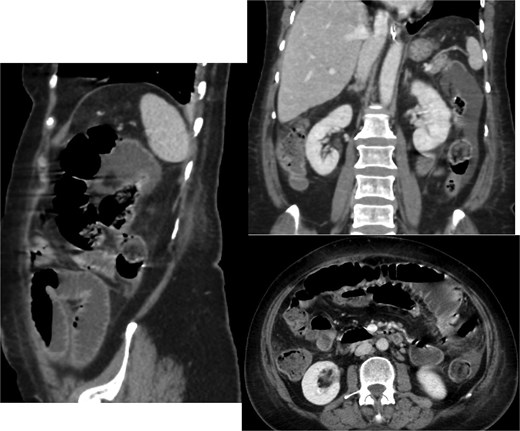

A CT scan of the abdomen revealed (Fig. 1):

A thickened gallbladder with a cholecystoduodenal fistula

A 22-mm gallstone impacted in the distal ileum causing high-grade small bowel obstruction

No signs of bowel ischemia, pneumoperitoneum, or intra-abdominal collections

No evidence of diverticulitis

Contrast-enhanced CT scan of the abdomen and pelvis showing the small bowel loops are dilated reaching up to 35 mm. There is a transition zone with 22 mm gallstone in the distal ileum with distally collapsed ileal segments and collapsed large bowel loops representing high-grade obstruction. The gallbladder appears irregular with thickened wall and significant surrounding fat stranding. There is a fistula between the gallbladder and the second part of the duodenum.